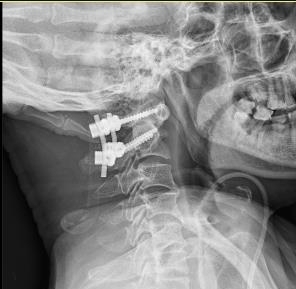

术前与术后对比图

经过充分的术前准备,由肖丹博士、黄勇兄副主任和我院张勇华主任及骨科一区团队共同为黄先生进行了手术治疗。术后黄先生顺利恢复,四肢麻木、乏力显著好转,排尿、排便恢复正常。出院时黄先生称赞道:多亏了省人医的帮扶专家,可以让自己在家门口享受到省级医院的待遇!